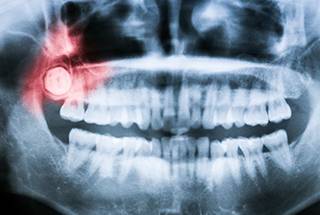

Wisdom Teeth Removal

Impacted or misaligned wisdom teeth can lead to pain, infection, and crowding. Our team provides expert wisdom tooth assessments and extractions, ensuring a smooth and comfortable experience.